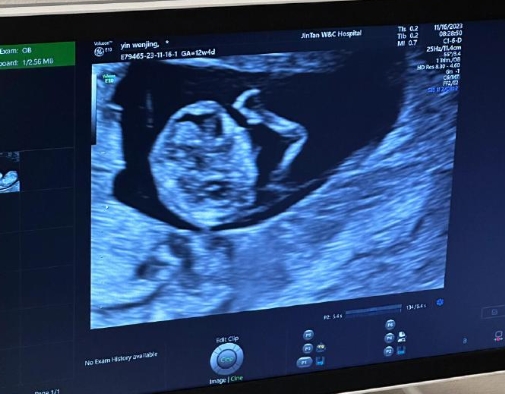

孕早期(通常指妊娠6-10周)的彩超主要用于确认宫内妊娠、排除宫外孕、监测胎心搏动及胚胎发育情况。彩超的超声波能量较低,且检查时间短(通常3-5分钟),目前研究未发现其对胎儿有致畸或发育不良的风险。

经阴道彩超:无需憋尿,图像更清晰,但仅适用于孕早期(尤其妊娠6-8周),需严格消毒探头以避免感染。